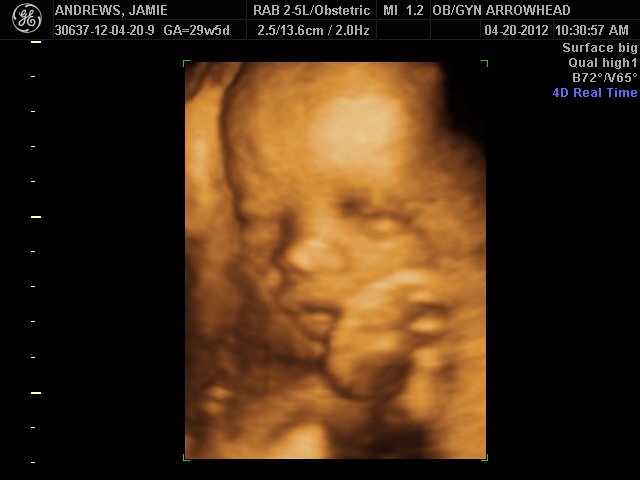

We offer complimentary 3D/4D Ultrasounds to all our OB patients around 30 weeks! The following photos are some examples of our work, shown with permission from our patients.